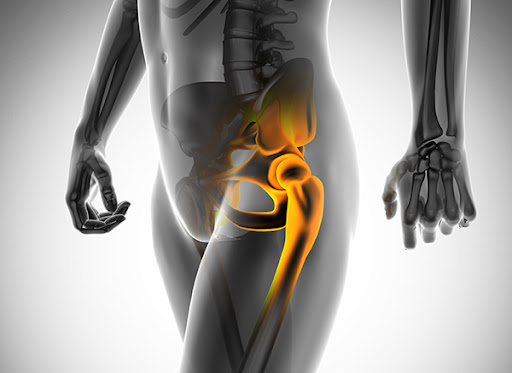

고관절 수술은 많은 사람들에게 필요한 복잡한 수술입니다. 나이가 들면서 또는 외상으로 인해 고관절의 기능이 떨어지면, 수술이 불가피해질 수 있습니다. 하지만 이러한 수술이 끝난 뒤에도 많은 이들이 어떤 과정을 거쳐 회복할 수 있을지에 대한 걱정이 많습니다. 이 블로그 글에서는 고관절 수술 후 회복기간과 단계별 재활 과정에 대해 상세히 알아보겠습니다. 정확한 정보를 통해 여러분의 회복 과정이 더욱 원활해지길 바랍니다.

고관절 수술 후 회복기간은 많은 요인에 따라 달라질 수 있습니다. 환자의 나이, 건강 상태, 수술 유형 등이 이에 포함됩니다. 고관절 수술의 전형적인 기간은 수술 후 6주에서 6개월까지 다양할 수 있습니다. 이 시간 동안 몸은 점진적으로 회복되며, 환자는 일상생활로 복귀할 수 있게 됩니다.